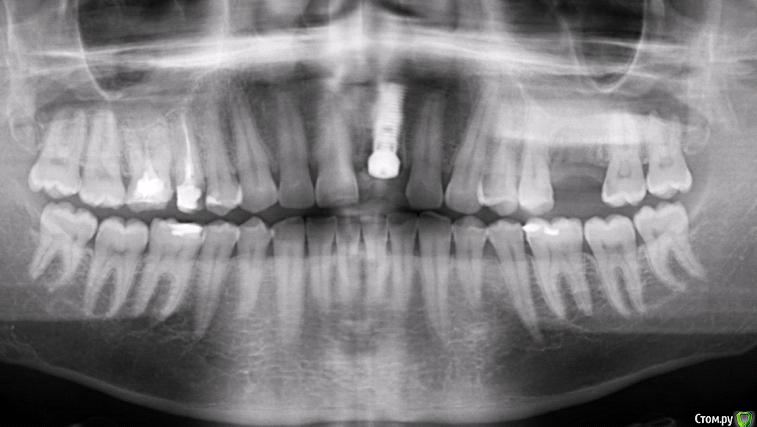

Популярный пост Фарид Расулыч Опубликовано 20 декабря, 2014 Популярный пост Поделиться Опубликовано 20 декабря, 2014 (изменено) Пациент обратился с проблемой, на производстве выбило зуб полетевшей в лицо "фиговиной". При осмотре коронка сломана глубоко под десну. Принято решение удалять и имплантировать с одномоментным временным протезированием. Работа производилась в конце смены, поэтому фоткать было особо некогда. Но кое что заснял. Удалил корень, имплантировал (заглубил имплант), подшил маленькую сст-шку (пожалел что маленькую, надо было жиренй), снял слепок (десневой маски под рукой не было, модель вся из гипса), сделал на обычном абатменте времяшку (были под рукой только обычные абатменеты, на них и воспроизводил сию лепнину), прикрутил. Самовыводы: не торопиться, сст жирней, времяшки не на обычных абатментах, ибо жалки да и пробивает метал. Через какое то время наверно переделаю времянку и зениты подровняю, но пациента все устраивает. Что скажете вы?? Изменено 20 декабря, 2014 пользователем Фарид Расулыч 23 Ссылка на комментарий

Sahan Опубликовано 20 декабря, 2014 Поделиться Опубликовано 20 декабря, 2014 Какой диаметр имплантата? Куда выходит шахта? Ссылка на комментарий

Фарид Расулыч Опубликовано 20 декабря, 2014 Автор Поделиться Опубликовано 20 декабря, 2014 3,75 х 16мм. Ставил по оси зуба. Ссылка на комментарий

kriokov Опубликовано 20 декабря, 2014 Поделиться Опубликовано 20 декабря, 2014 3,75 х 16мм. Ставил по оси зуба.По снимку показалось 13 мм максимум Ссылка на комментарий

Фарид Расулыч Опубликовано 20 декабря, 2014 Автор Поделиться Опубликовано 20 декабря, 2014 Тем не менее это 16. Зуб небно уходит. Я как то заказал 8 имплантов по 16 мм для all on four, пациент не пришел) пришлось реализовывать импланты)) 2 Ссылка на комментарий